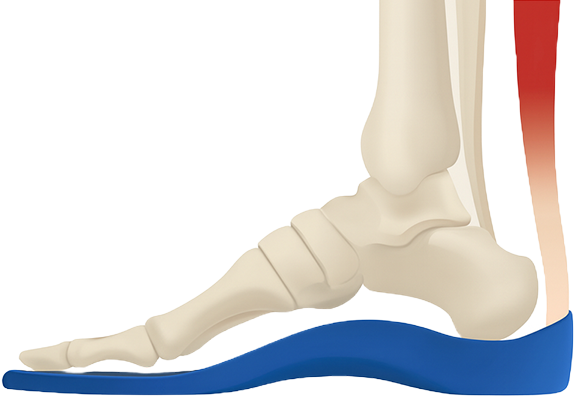

염증이 생긴 아킬레스건염에 미치는 압력을 감소시키기 위해

뒷굽이 2~3cm 높은 치료용 1:1 맞춤형 깔창을 착용하여

하중을 분산시켜야 합니다.